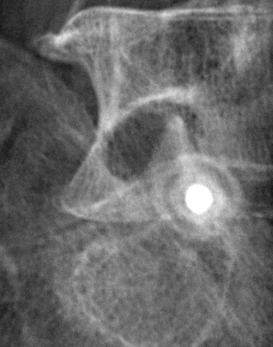

Infiltration de l'articulation omo-humérale (épaule).

Après ponction directe de l'articulation, il est injecté du produit de contraste afin de s'assurer de la position intra-articulaire de l'aiguille avant d'injecter l'anti-inflammatoire.